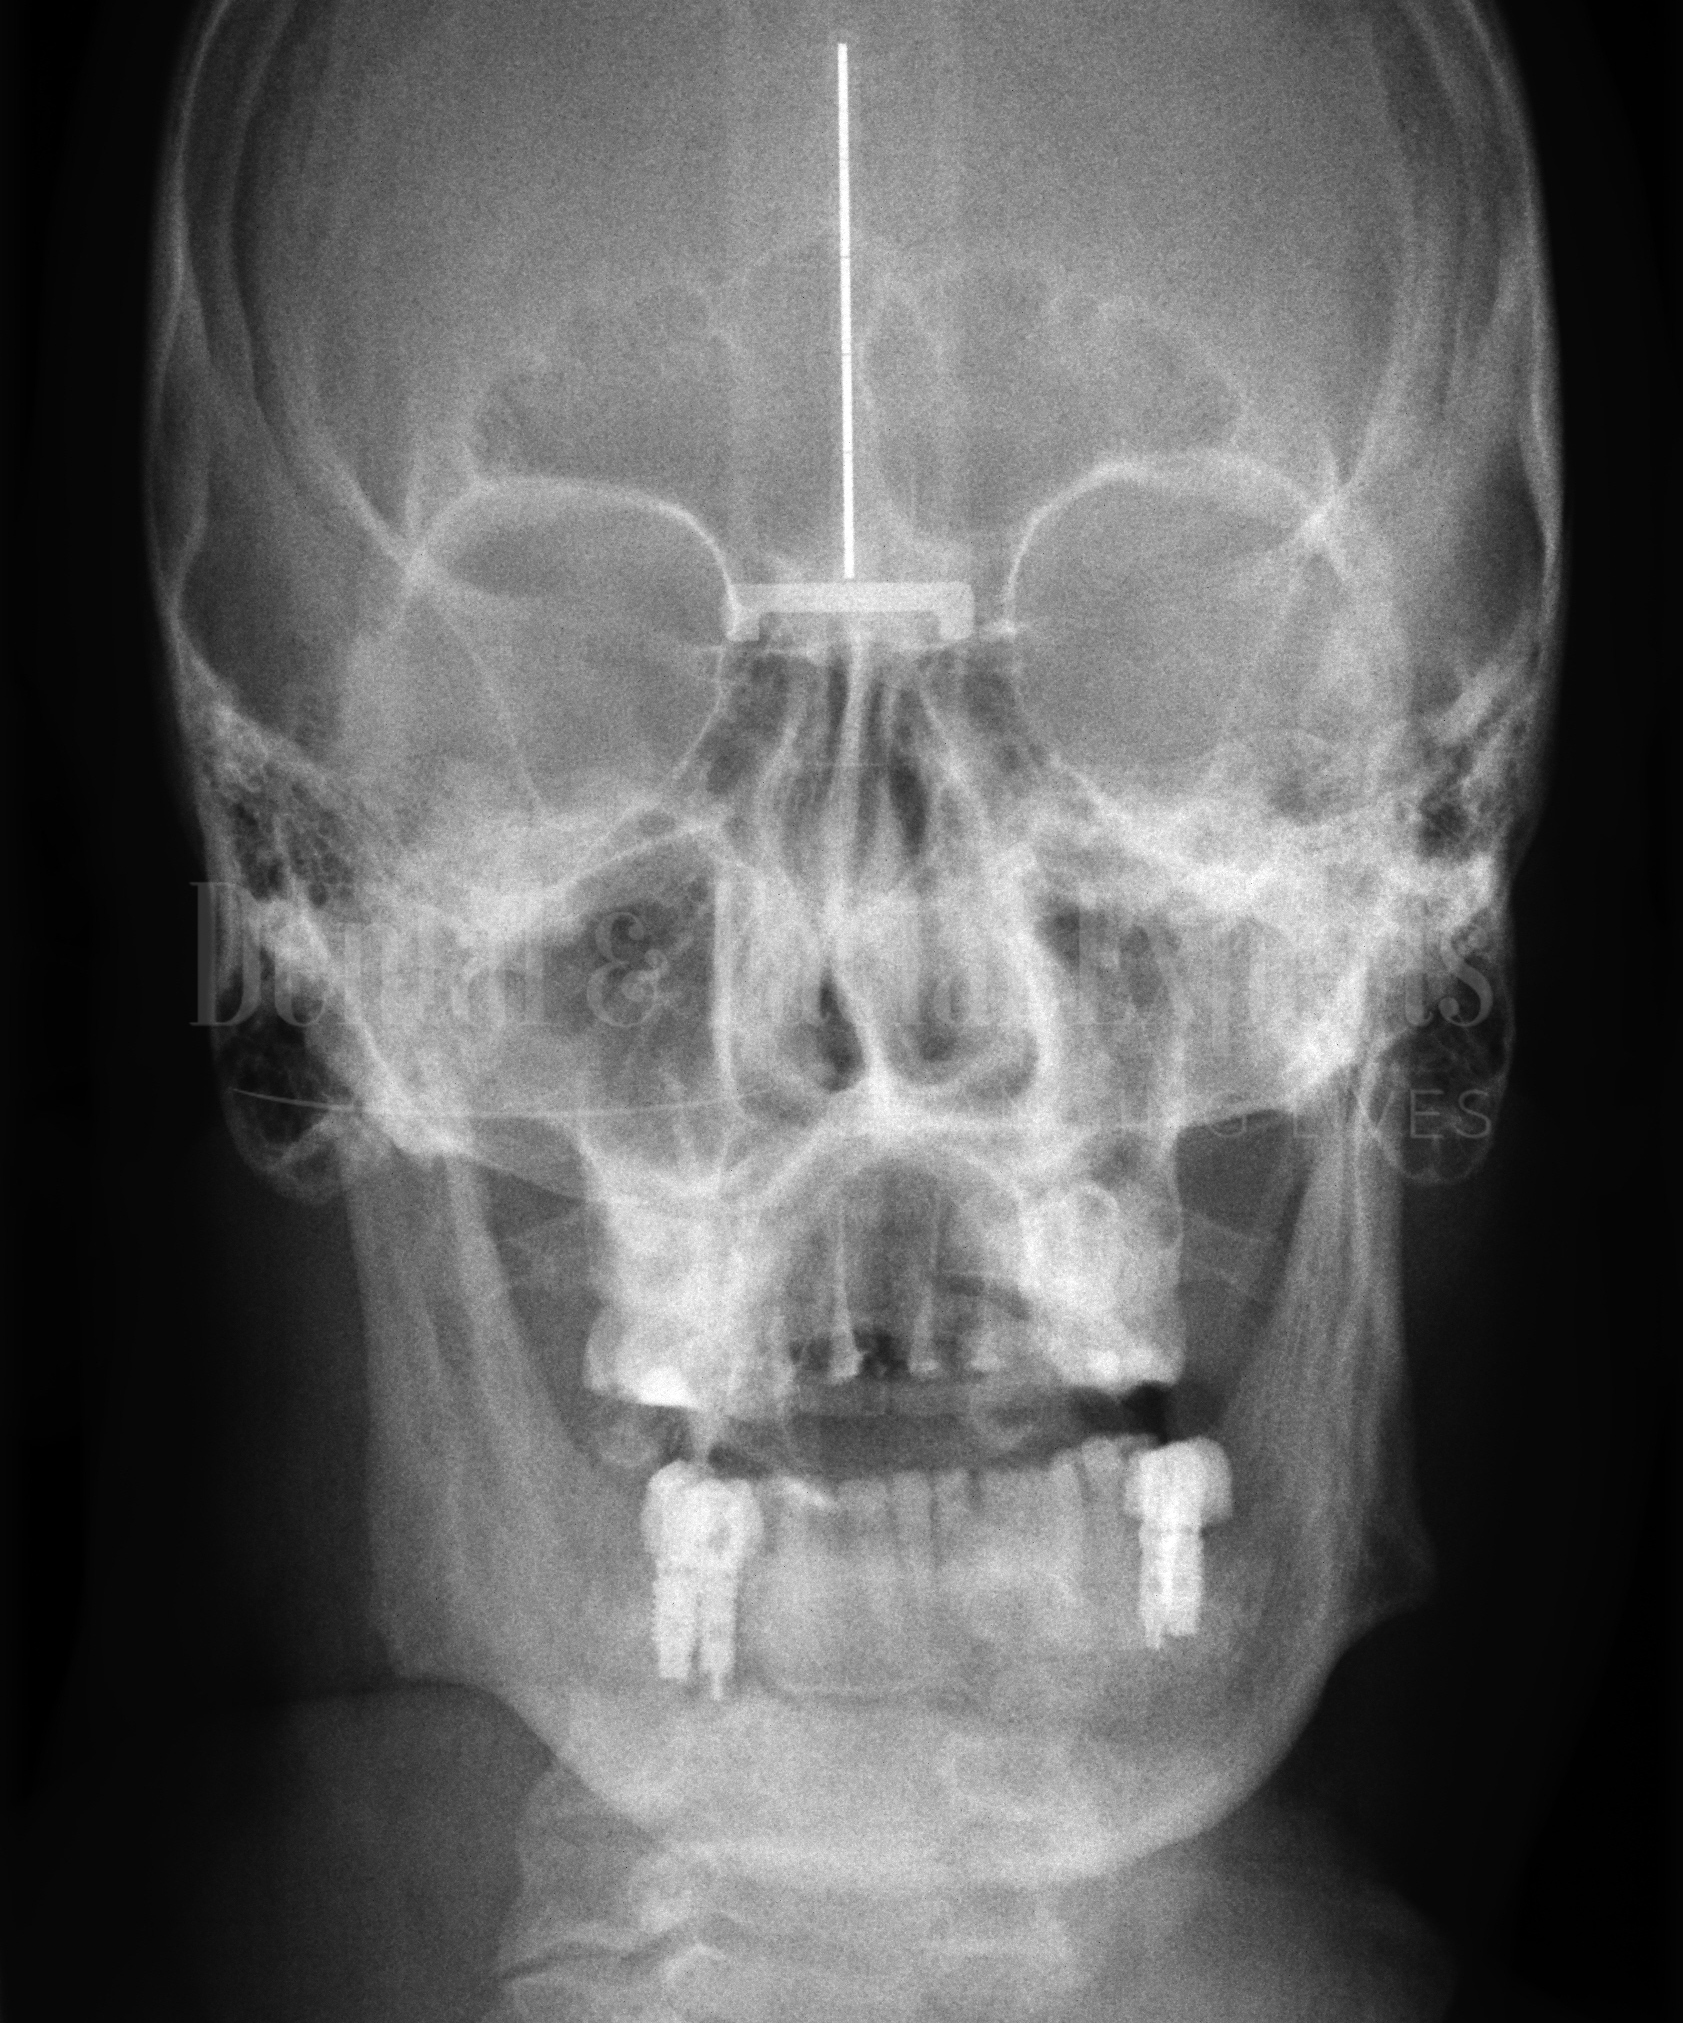

JOSE-3-Cópia

JOSE 3

TRATAMENTO

• APNEIA OBSTRUTIVA DO SONO

• CIRURGIA ORTOGNATICA BI-MAXILAR

• MENTOPLASTIA